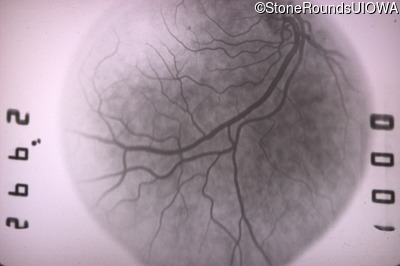

Fluorescein Angiography - Right - 20/25 +2 sc

Exemplar